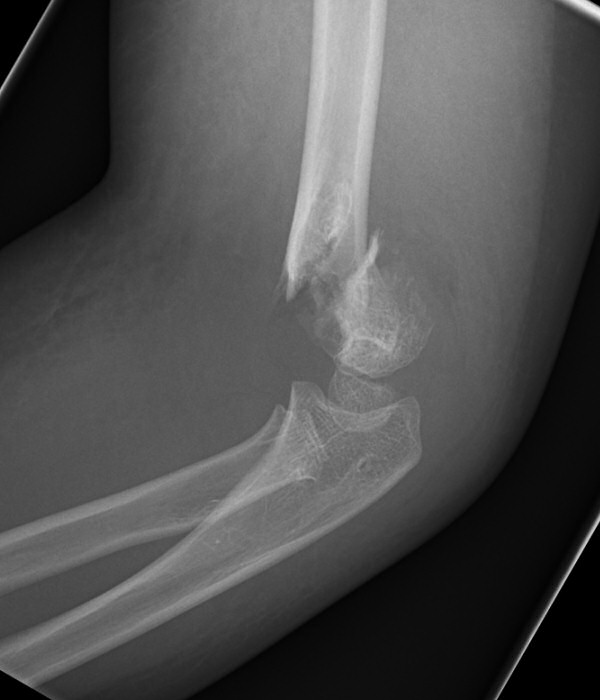

Suprakondylar humerusfraktur, Gartland 3, före och efter operation med stiftning